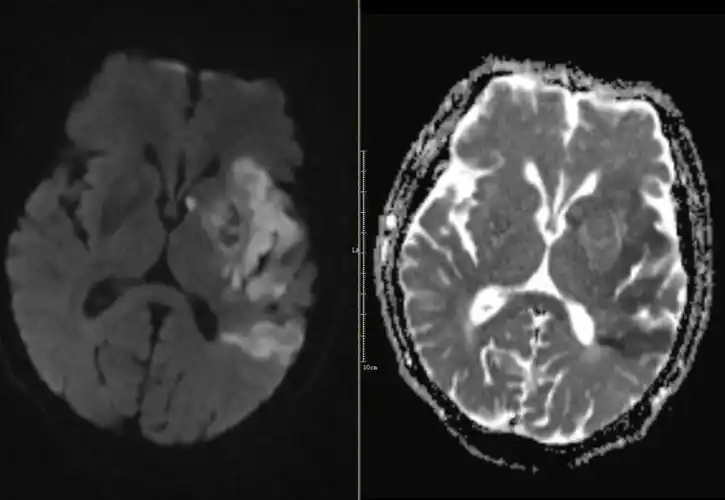

67超急性期大面积脑梗死ct平扫表现

通过ct平扫和核磁t2及flair像,均发现病灶显示不是很明显,容易造成漏